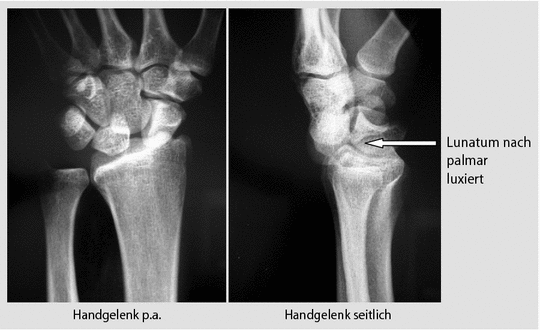

Luxationen Der Handknochen Verletzungen Und Vergiftung Msd Manual Ausgabe Fur Patienten